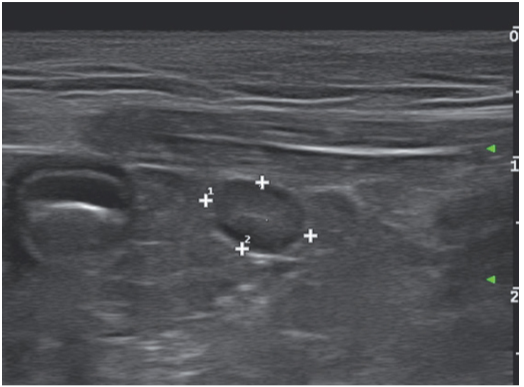

超声检查的可以定位隐睾,依次从肾脏尾极至阴囊处进行扫查。通过睾丸纵膈等睾丸的特征性结构来寻找睾丸,这种方法也有失败的可能,特别是在睾丸发生癌变的时候(图10)。

一只七岁未去势暹罗猫患有细菌性前列腺炎并发膀胱炎。超声影像上可见其前列腺位于膀胱尾侧,为一直径3cm的卵圆形团块样结构,内部低回声,外部轮廓回声较高(图11)。